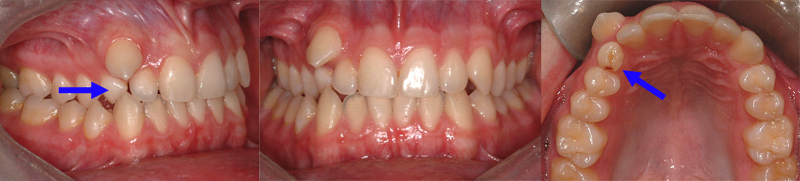

Canine permanente supérieure droite qui sort au-dessus d’une dent temporaire qui n’est pas tombée (flèche). Il est parfois indiqué d’extraire des dents temporaires pour faciliter l’éruption des dents permanentes.